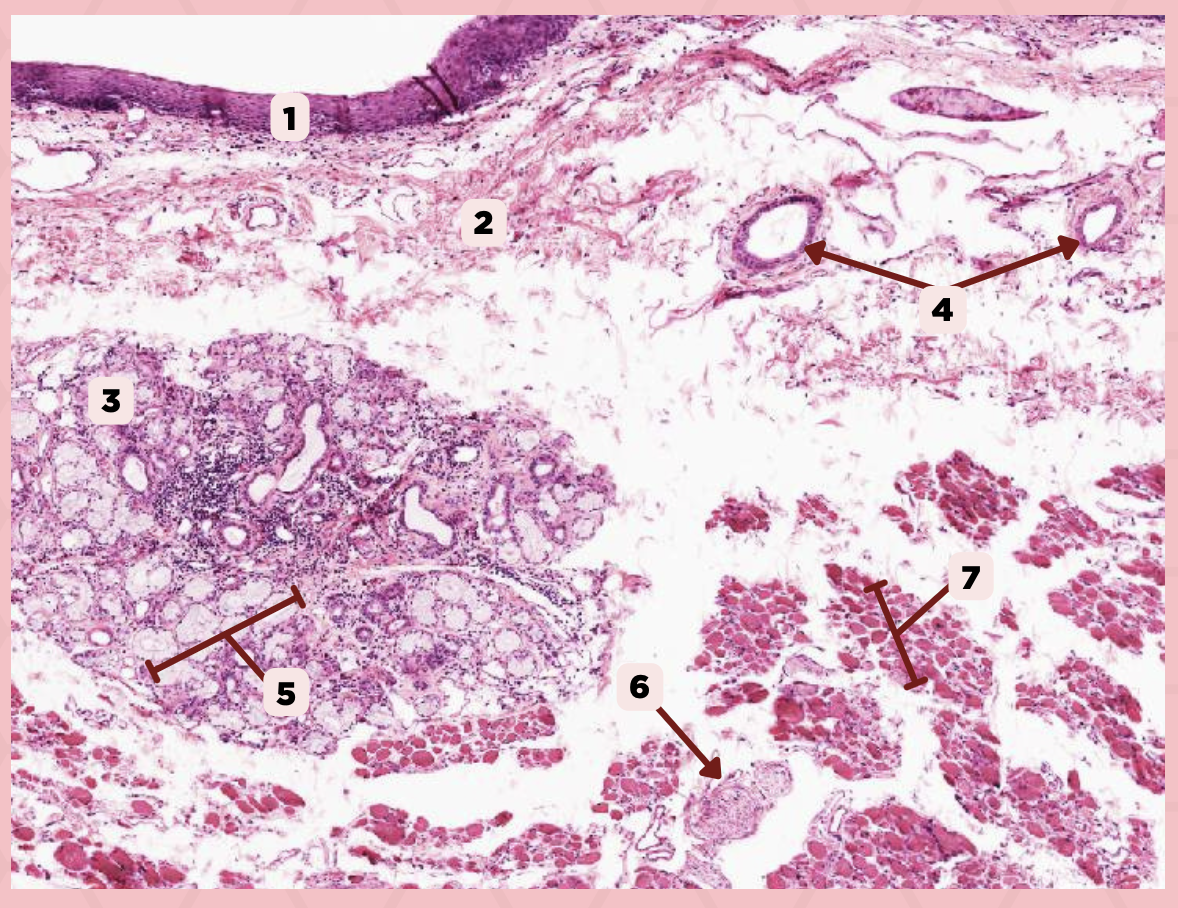

Cheek

Identify the specimen.

Mucosa

Identify the structure labeled as 1.

Lamina Propria

Identify the structure labeled as 2.

MALT

Identify the structure labeled as 3.

Blood Vessels

Identify the structure labeled as 4.

Buccal Glands

Identify the structure labeled as 5.

Nerve

Identify the structure labeled as 6.

Muscle Fascicles

Identify the structure labeled as 7.